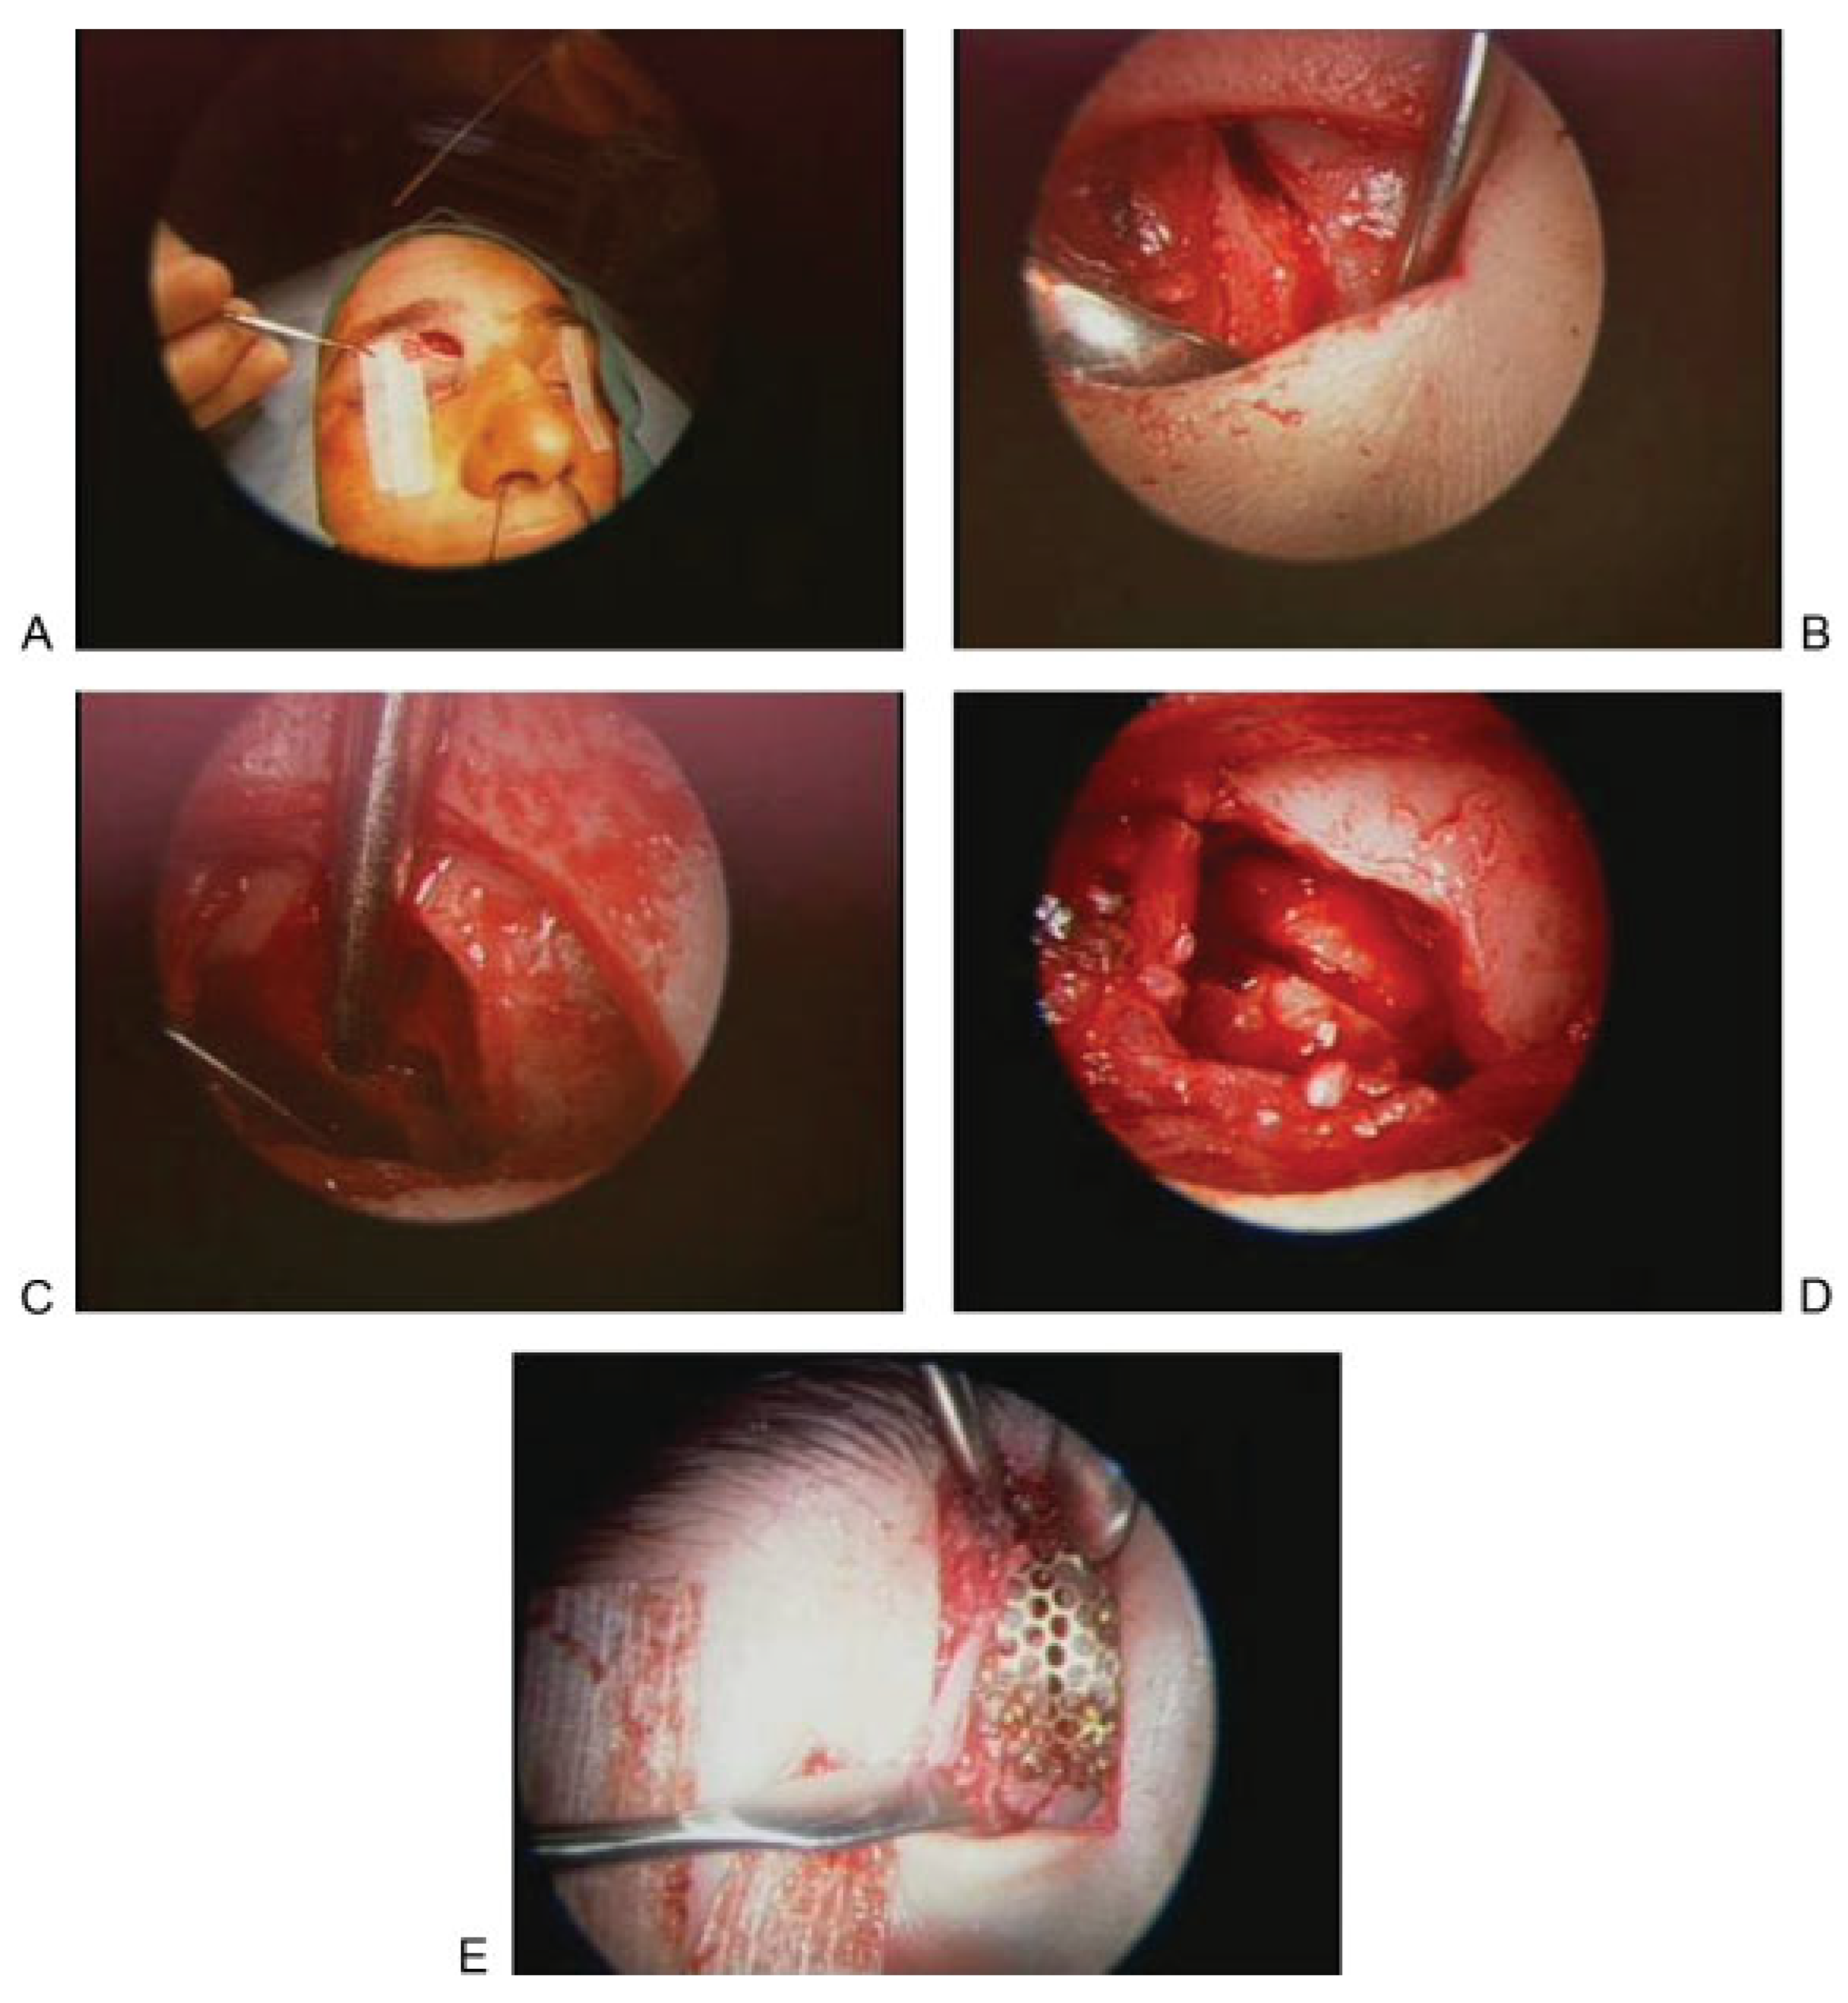

Figure 2.

Trephination approach for endoscopic assessment of the posterior wall. (A) Incision. (B) Exposure of fracture. (C) Exposure of sinus. (D) Exposure of posterior wall of frontal sinus. (E) Repair.